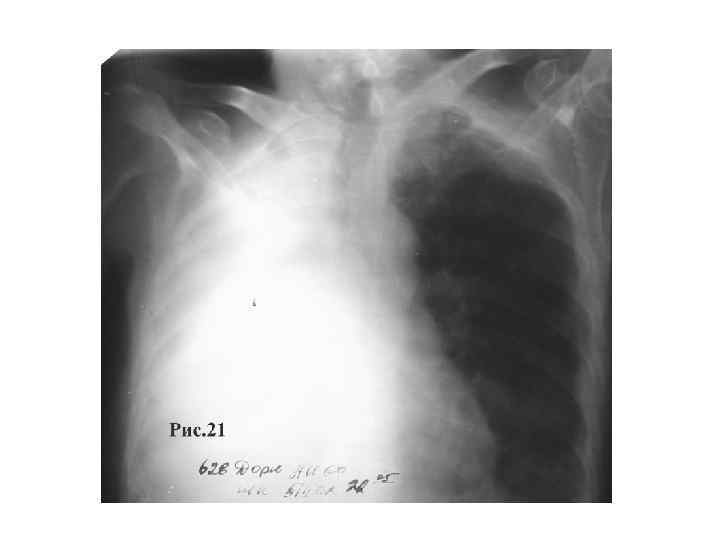

ДИАГНОСТИКА • Центральный рак – гиповентиляция, затем ателектаз обтурационный (уменьшение объема, уменьшение экскурсии, ослабление голосового дрожания, притупление звука перкуторного, ослабление везикулярного дыхания вплоть до его отсутствия). • Периферический – синдром уплотнения легочной ткани.

ЦЕНТРАЛЬНЫЙ РАК ЛЕГКОГО